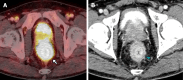

Case summary: Three patients with secondary RLP due to prostatic adenocarcinoma presented with varied clinical features. The first patient, a 76-year-old man with advanced prostate cancer, had rectal pain and incontinence. MRI showed diffuse prostatic invasion and significant rectal wall thickening with a characteristic "target sign" pattern. The second, a 57-year-old asymptomatic man with elevated prostate-specific antigen levels and a history of prostate cancer exhibited rectoprostatic angle involvement and rectal wall thickening on MRI, with positron emission tomography/computed tomography PSMA confirming the prostatic origin of the metastatic spread. The third patient, an 80-year-old post-radical prostatectomy, presented with refractory constipation. MRI revealed a neoplastic mass infiltrating the rectal wall. In all cases, MRI consistently showed stratified thickening, concentric signal changes, restricted diffusion, and contrast enhancement, which were essential for diagnosing secondary RLP. Biopsies confirmed the prostatic origin of the neoplastic involvement in the rectum.